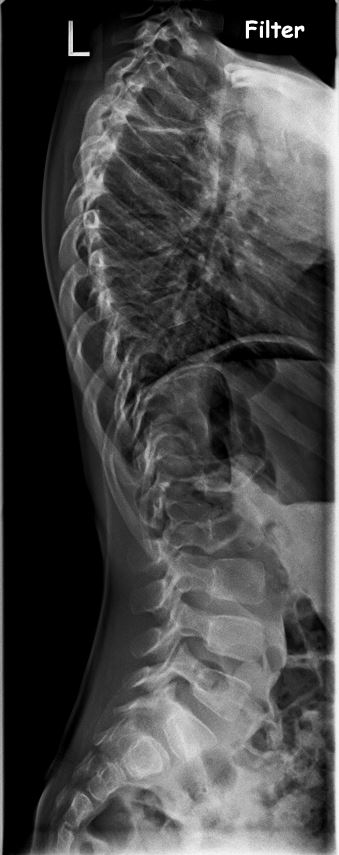

PS. Hier mal die RÖ-Bilder

RB.JPG

RB.JPG (41.84 KiB) 7852 mal betrachtet

RBS.JPG

(47.29 KiB) Noch nie heruntergeladen

Bei meiner 4 Jährigen Tochter wurde vor einigen Tagen ein Halbwirbel im 6 BWS festgestellt.

Dadurch natürlich eine Koliose leider haben wir keine Angaben wie hoch die Gradzahl ist.

Also für mich wäre das definitiv noch keine OP Indikation. Ich würde versuchen die Verschlechterung mit einem Korsett aufzuhalten. Wenn alles so bleibt werden mit hoher Wahrscheinlichkeit keine Probleme auftreten. Aufgrund der Höhe der Krümmung bei T6 geht sicher nur ein Nachtkorsett. Das sollte aber ausreichen. Sollte die Krümmung im Verlauf der Jahre doch zunehmen, kann man die Op immer noch durchführen. In der Regel kann der Verlauf jedoch gestoppt werden.